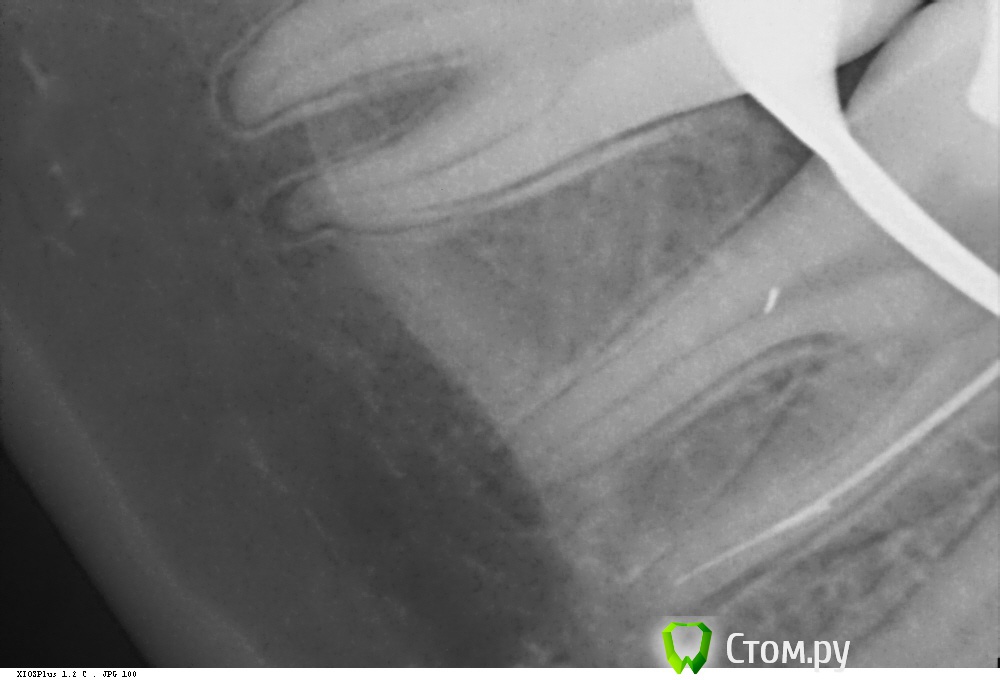

Shaid Опубликовано 29 января, 2014 Автор Поделиться Опубликовано 29 января, 2014 (изменено) Рис.1 Пульпит 2.5. Ничего необычного нет, просто понравился снимок) Возможно, кому-то покажется, что каналы перерасширены?Рис.2,3 Тоже пульпит пятерки. Тот случай, когда спредер залезает в канал, а 15 штифты - нет, гнутся , в результате чего картинка вызывает ассоциации, будто в каналы засунули по две дренажной трубки из хирургии. Изменено 29 января, 2014 пользователем Shaid Ссылка на комментарий